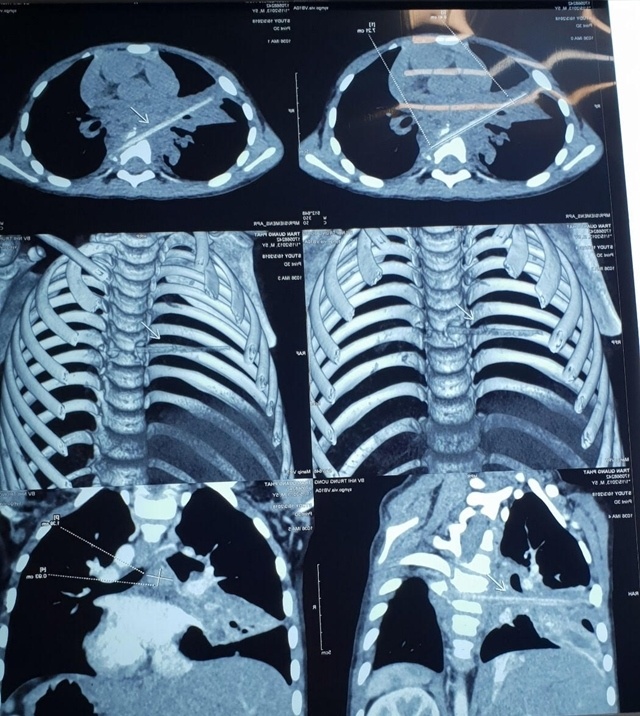

| Hình ảnh que nứa dài 9 cm trên phim chụp. Ảnh: Lê Mai. |

Hình ảnh chụp vi tính cắt lớp sau đó cho thấy bệnh nhi có một dị vật dài nhọn kích thước 72x4 (mm) tại vị trí nhu mô thùy phổi ở thùy giữa phổi phải.

Dị vật này đi từ trước ra sau, xuyên qua khe giữa 2 thân đốt sống 6,7 và làm vỡ thân đốt sống. Khi nằm lại trong cơ thể, dị vật gây phản ứng thâm nhiễm viêm trung thất sau quanh đốt sống 6,7. Đây cũng chính là nguyên nhân khiến bé Minh phải vào viện vì viêm phổi trong suốt 8 tháng.